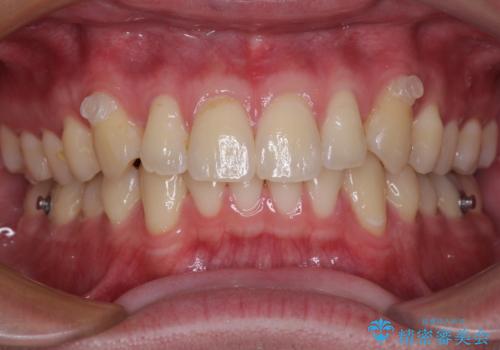

- 前歯のデコボコと突出感を気にして来院された患者様です。

極力目立たない装置を希望とのことで、インビザラインを用いて非抜歯で矯正治療を行うこととしました。

事前に親知らず4本を抜歯し、多少歯列を後方に移動できるように準備をした上で、なるべく歯と歯の間を削ることなくデコボコを解消できるように計画しました。